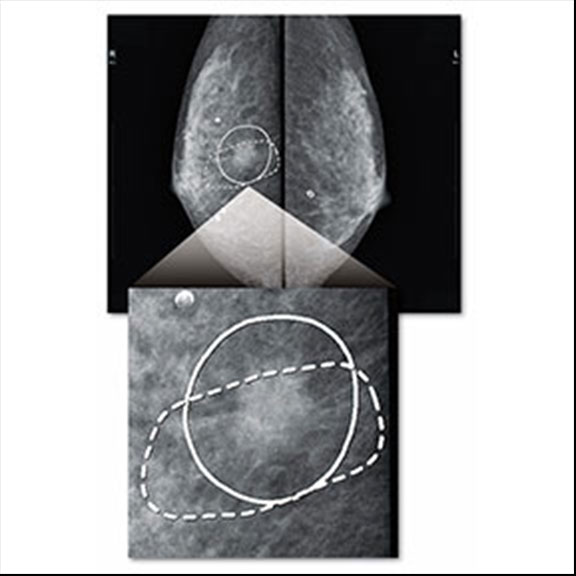

マンモグラフィーCAD機能

マンモグラフィ診断支援装置 NEOVISTA CAD typeM

マンモグラフィー診断支援ソフトウェアライセンスMGCAD-i

独自のアルゴリズムに基づくマンモグラフィー診断支援装置です。マンモグラフィー検診画像の「見落とし防止」や「読影時間の短縮」を強力にサポートします。